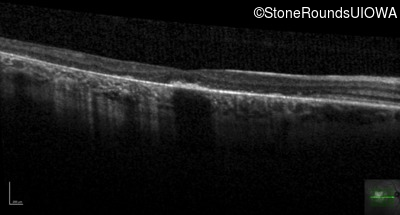

Age at visit: 38 years

OD OS

This 38 year old man first noticed poor vision in dim light when he was five years old. His visual acuity began to fall in his early 30's.

Macular Disease WDR19 His344Arg CAT>CGT Ser485Ile AGT>ATT AR